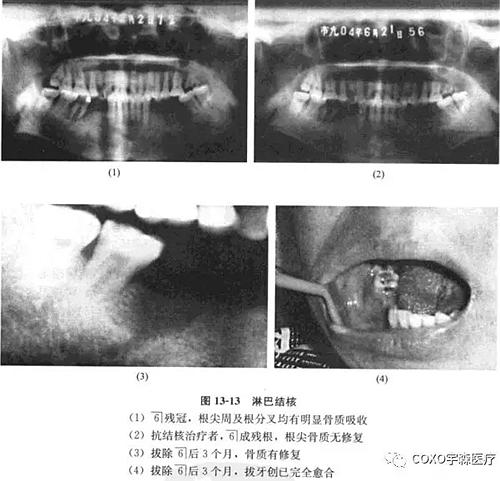

病例: 女性,48歲,右下后牙區(qū)腫痛2個(gè)月,曾在某醫(yī)院診斷為根尖周炎,抗炎治療無效,遂于6]近中取活檢,診斷為炎癥性改變,結(jié)核可疑,后轉(zhuǎn)來我院。

檢查:7-3]牙齦腫脹,54]缺失,6]呈殘冠狀,近中齦有炎性肉芽組織。x線片示:6]殘冠,根尖周及根分叉均有明顯骨質(zhì)吸收,雙頜下淋巴結(jié)腫大,質(zhì)中偏硬,臨床診斷為6]根尖周炎,頜下淋巴結(jié)核可能。

經(jīng)右頜下淋巴結(jié)穿刺,見上皮細(xì)胞、多核巨細(xì)胞和淋巴細(xì)胞,結(jié)合臨床及6]近中原切片,認(rèn)為病變符合結(jié)核診斷。行抗結(jié)核治療,3個(gè)月后復(fù)查,臨床頜下淋巴結(jié)顯著縮小,口內(nèi)牙齦腫脹基本消失,無任何創(chuàng)面,殘冠已折斷,僅剩6]殘根,X線示根尖周骨質(zhì)無修復(fù)現(xiàn)象。遂拔除司殘根,繼續(xù)行抗結(jié)核治療,3個(gè)月后骨質(zhì)有修復(fù),拔牙創(chuàng)已完全愈合(圖13-13)。

分析與評述

結(jié)核病可出現(xiàn)在口腔軟組織,也可以出現(xiàn)在頜骨組織內(nèi),臨床不多見。結(jié)核病出現(xiàn)在軟組織時(shí)可表現(xiàn)為潛穴性潰瘍,疼痛癥狀十分顯著。本病例最初表現(xiàn)為牙痛及牙齦腫塊,6]為死髓牙, 線片示根尖骨質(zhì)有吸收,牙齦組織切片僅提示結(jié)核可疑;后經(jīng)下頜下淋巴穿吸活檢6]區(qū)病損亦確認(rèn)為結(jié)核。經(jīng)抗結(jié)核治療后逐步好轉(zhuǎn),口內(nèi)腫脹消失,拔除6]后骨質(zhì)也逐漸得以修復(fù)。

本病例十分不典型,無疼痛癥狀;局部又存在死髓牙,極易誤診為根尖周病。其最后診斷依賴于下頜下淋巴結(jié)病理檢查,提示在診治根尖周病時(shí)必須進(jìn)行全面的口腔頜面部檢查而不僅僅限于牙及牙槽部。